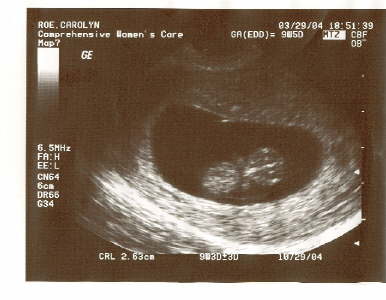

Baby Shot 2